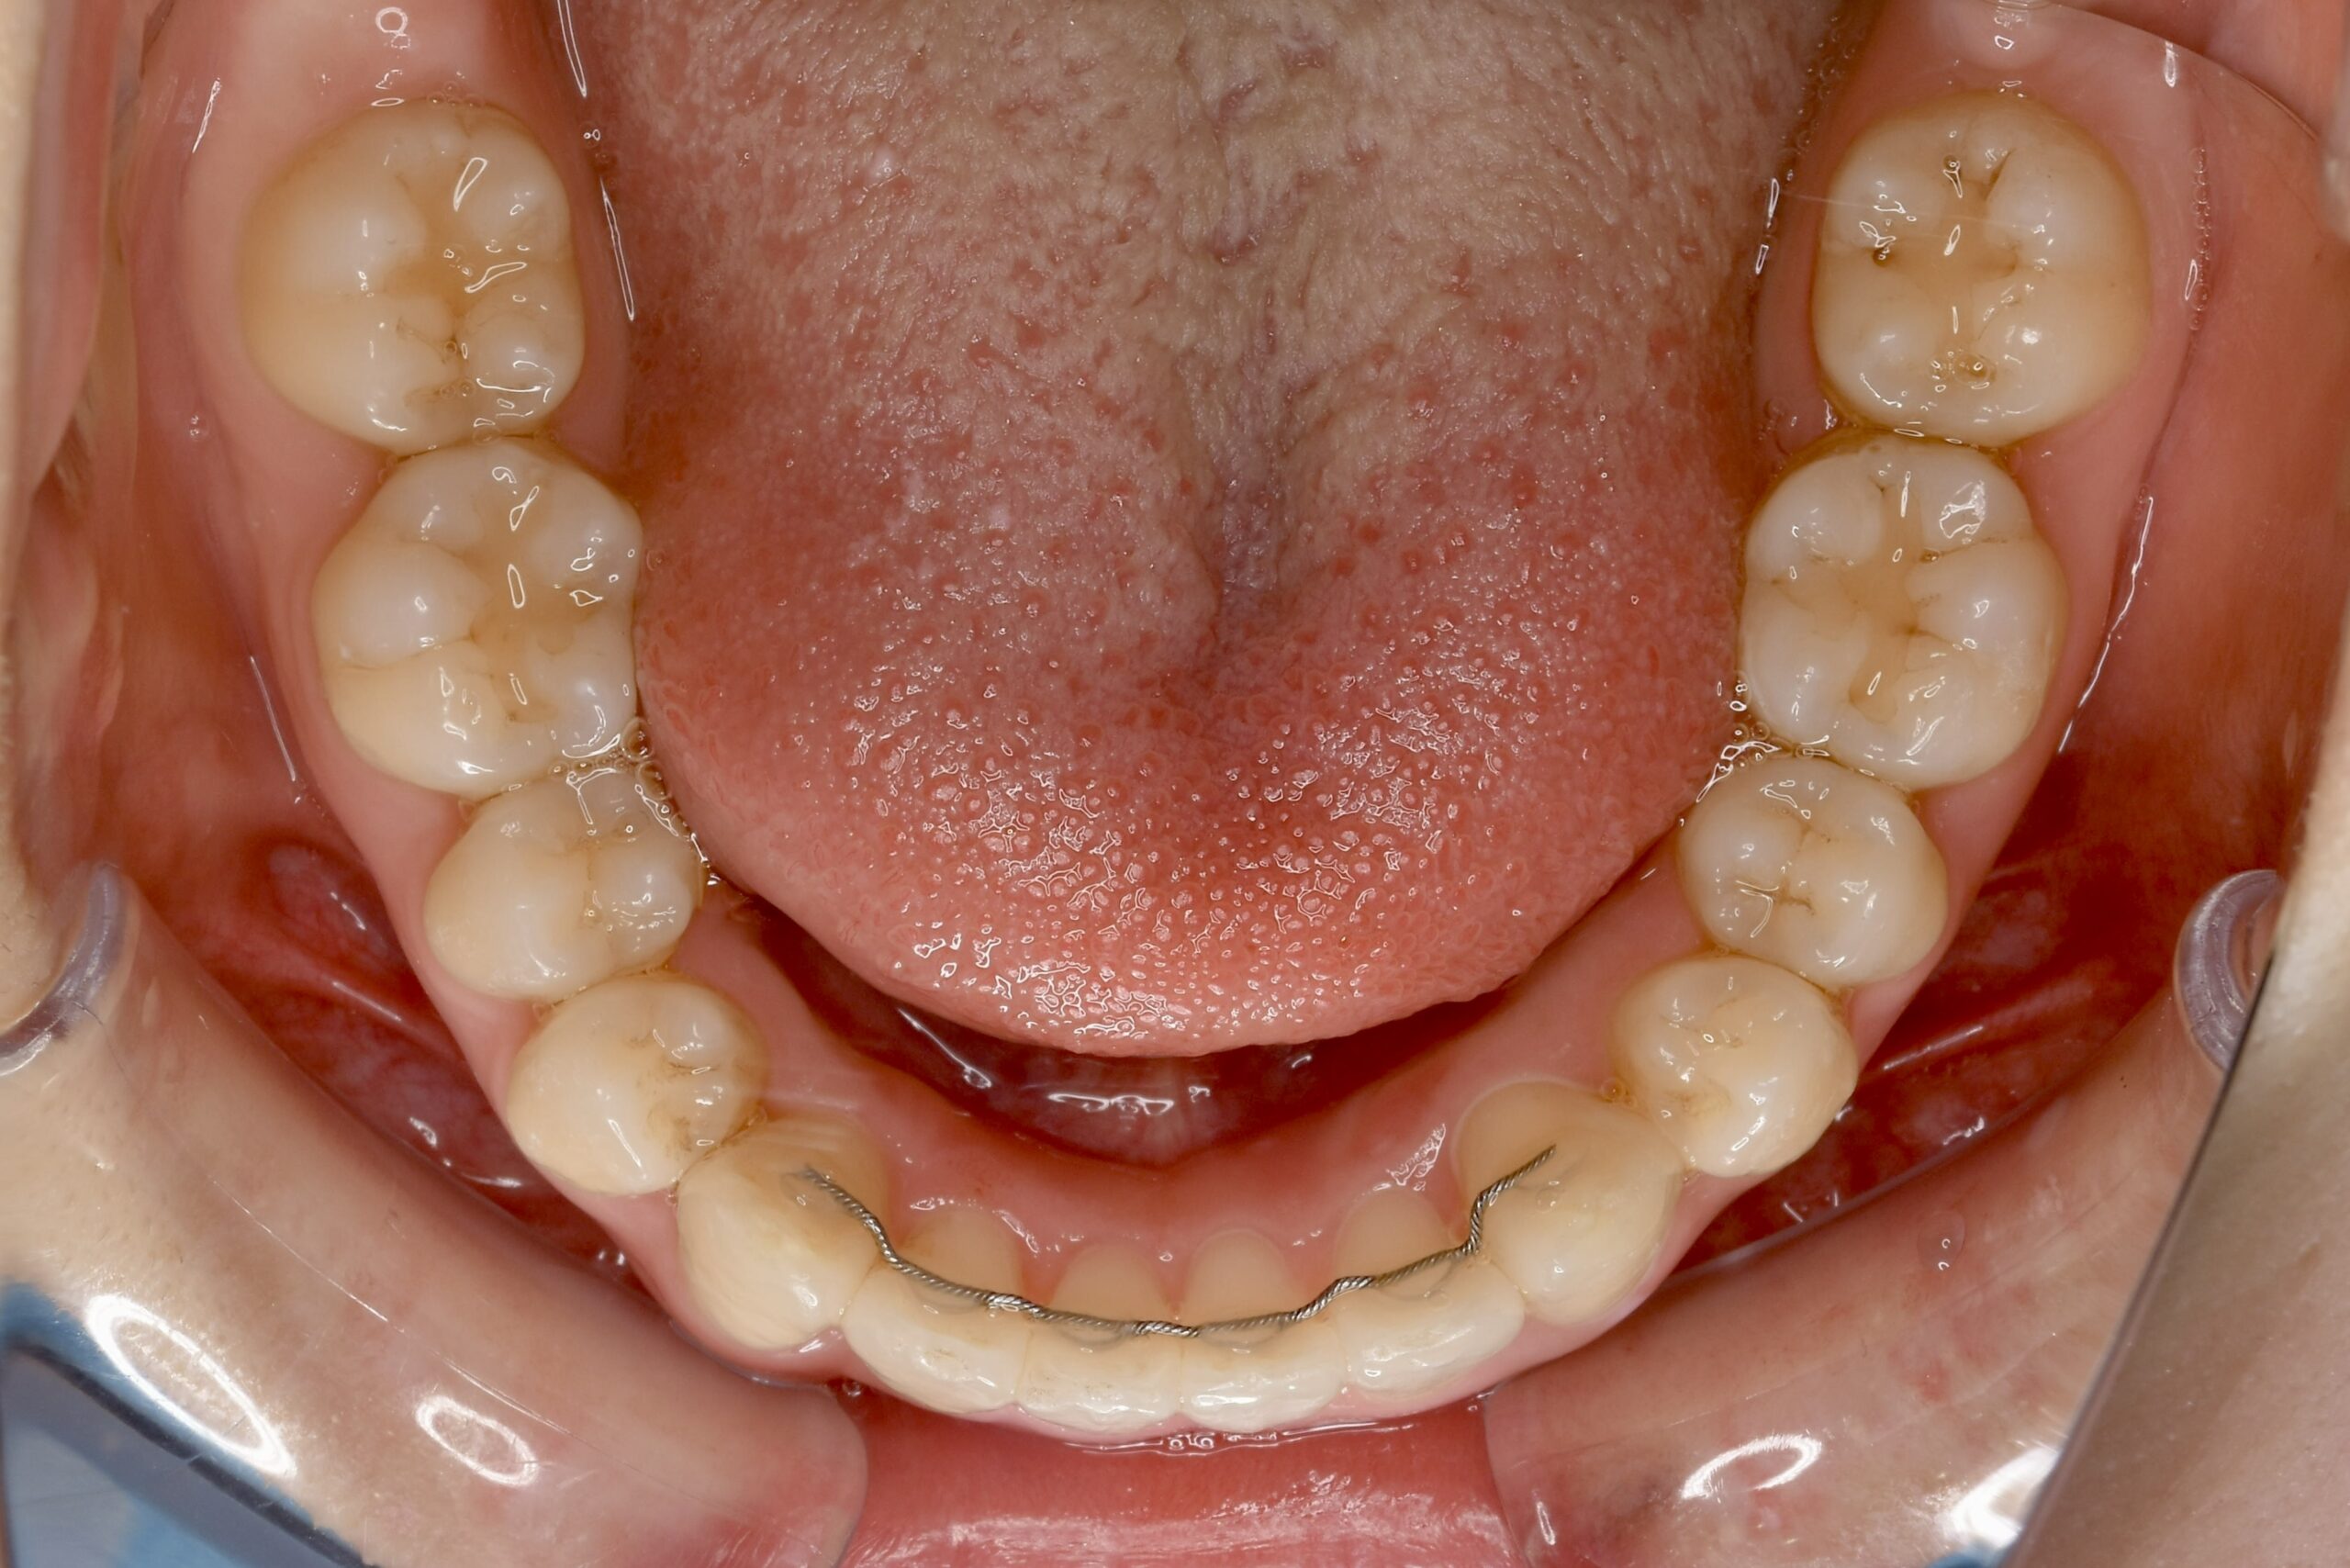

21歳 女性 治療期間:1年1ヶ月

叢生(ガタガタ)

マウスピース矯正装置(インビザライン)

BEFORE

AFTER

上下とも歯並びの横幅を広げながら、でこぼこを解消しました。

マウスピース矯正(インビザライン)

抜歯あり(智歯抜歯)

治療期間

1年1ヶ月